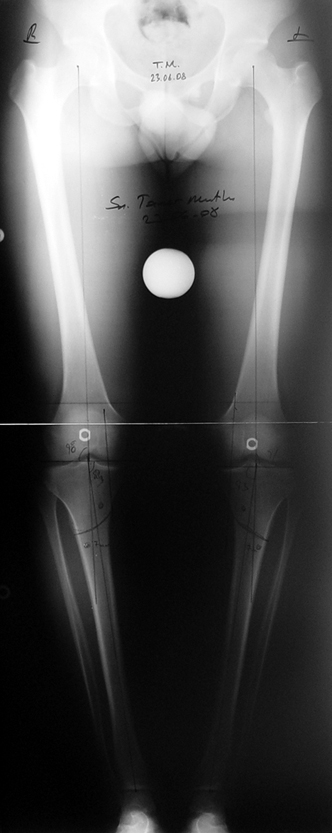

Postoperatif Bakım: Distraksiyona (Kemik parçalarının arasının birbirinden uzaklaştırılması yöntemi) 10. günde başlanır. Günde 4 defa 6 saatte bir 0.25mm uzatma yapılır. Operasyondan 1-2 gün sonra kalça ve diz çevresi hareketlere başlanır. Alt ekstremite kısalıklarının tedavisi uzun yıllar boyunca hem hasta hem de cerrah için zorluklarla dolu olmuştur. İlizarov’un distraksiyon osteogenezisi kavramını tanımlamasından sonra geliştirilen teknikler bu konuda yeni bir çağın öncüleri olmuşlar ve daha önceki yıllarda görülen komplikasyonların oldukça azaldığı uygulamalar olarak anılmışlardır.

Günümüzde ekstremite uzatma uygulamaları için tercih edilecek yöntemde aranan en önemli özellikler şöyle sıralanabilir; uygulama süresi, “alignment” (kemiğin anatomik ve mekanik aksı) sağlama , toplam ameliyat sayısı, rejeneratın refraktürden korunabilmesi, çivi dibi infeksiyonu ve sebep olabileceği komplikasyonların asgari miktarda tutulması, hareket açıklığının korunması, “iyileşme zamanı “, günlük hayattaki konfor ve uygulama maliyeti.

Biz son zamanlarda, seçilmiş vakalarda, uzatma sonrası uzunluğu ve “alignment’ı” korumak amacı ile unilateral dinamik aksiyel fiksatör ve kilitli intramedüller çivi kombinasyonunu tercih etmekteyiz. Bu yöntemin ön şartları medullanın en dar çapının 7 mm.’den geniş olması ve uzatma sonrası distalde en az 8 cm. uzunluğunda çivi kalabilmesidir. İntramedüller çivi hem uzatma esnasında femurun üzerine gelen makaslama ve bükülme kuvvetlerini nötralize etmekte hem eksternal fiksasyon süresini kısaltmakta, hem de yeni oluşan kemiği kırıklara karşı korumaktadır. Serimizde bir vakada subtrokanterik femoral osteotomi yapılmıştır. İntramedüller çiviye rağmen varus angulasyonu oluşması yönünde bir dezavantaj tespit etmedik.

İntramedüller çivi ve eksternal dinamik aksiyel fiksatör kombinasyonu teknik olarak standart İlizarov uygulamalarından daha zordur. Ancak şu avantajlar yöntemi cazip hale getirmektedir; eksternal fiksasyon süresinde kısalma, refraktüre karşı korunma, erken rehabilitasyon, azami hareket genişliği kazanma ve günlük yaşam konforu. Bu avantajlar artan maliyet , artan kan kaybı ve potansiyel derin infeksiyon gibi dezavantajların önüne geçmektedir. Sonuç olarak, bulgularımızın eşliğinde, intramedüller çivi üzerinden femoral uzatma tekniğinin güvenilir ve dayanıklı bir metod olduğunu ve bizce standart İlizarov uygulamalarına üstünlük sağlayan avantajlar getirdiğini söyleyebiliriz.